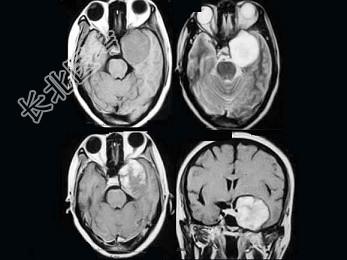

- 单项选择题女,47岁, 左侧面部麻木2个月余,伴阵发性头痛、耳鸣, MRI检查如图,最可能的诊断为 ( )

A、三叉神经纤维瘤

B、海绵状血管瘤

C、脑膜瘤

D、颅咽管瘤

E、胶质瘤